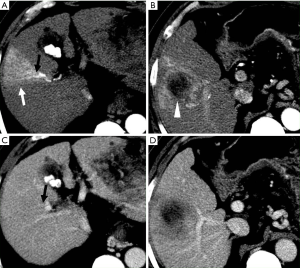

Evaluation of HCC with HAPS

HAP results in the heterogeneous enhancement of the hepatic parenchyma. The enhancement of HCC will be significantly reduced in the situation of serious HAPS due to a large amount of contrast medium flowing into the portal vein through the shunt. On the equilibrium phase, the characteristic washout and extension of the tumor can nonetheless be identified accurately. The equilibrium phase is most useful for diagnosis and delineation of HCC as an area of heterogeneous low density (intensity) (Figures 7,8). The presence of HAPS is not necessarily a contraindication to resection, ablative therapies or other liver-directed therapies, and the degree of resection or other therapy can best be determined in the equilibrium phase (22).